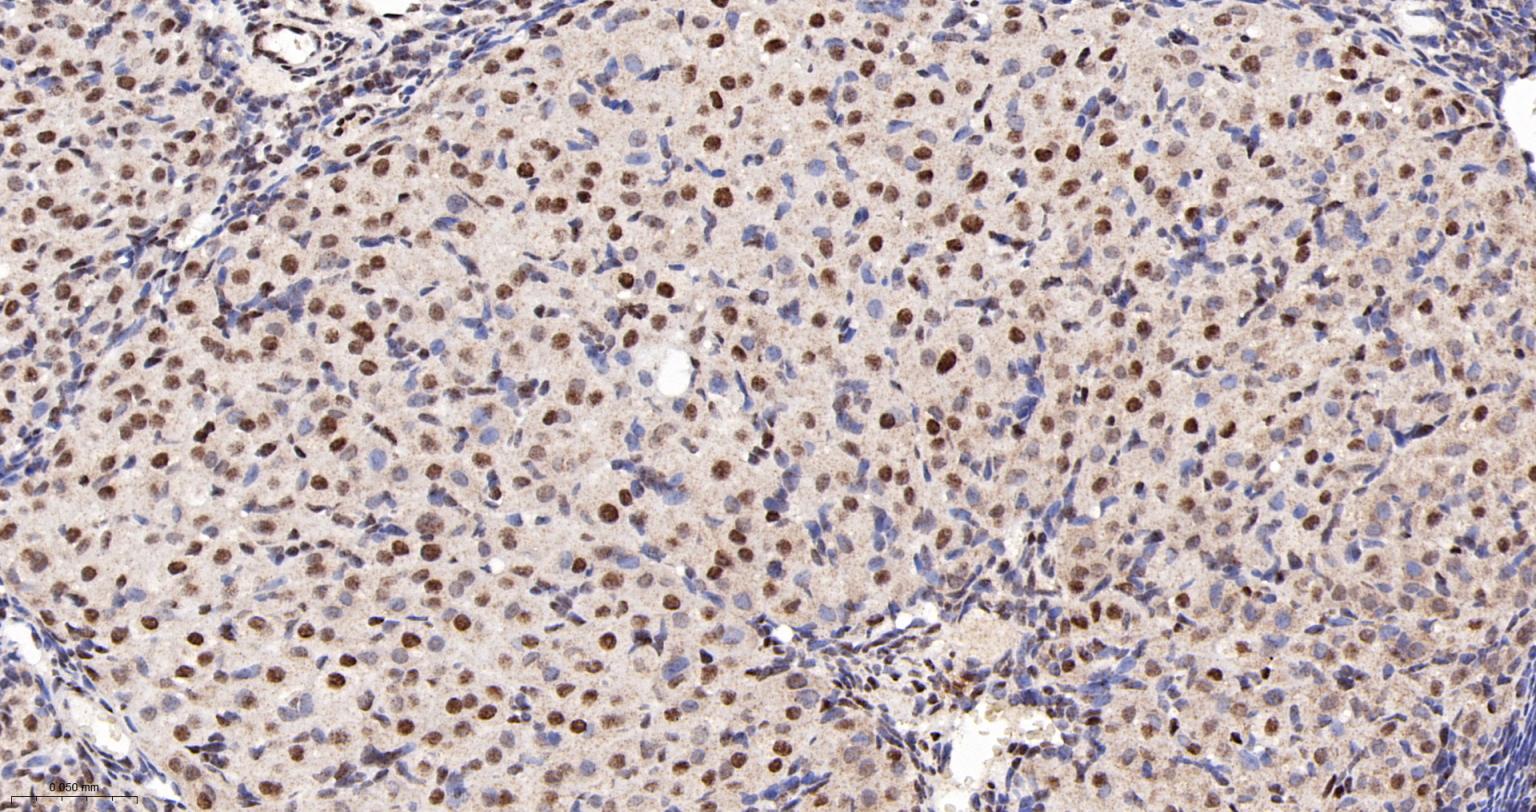

Paraformaldehyde-fixed, paraffin embedded Human Cerebrum; Antigen retrieval by boiling in sodium citrate buffer (pH6.0) for 15 min; The section was incubated with COUP-TF1 Monoclonal Antibody, Unconjugated (bsm-61615R) at 1:200 overnight at 4°C, followed by conjugation to the bs-0295G-HRP and DAB (C-0010) staining.